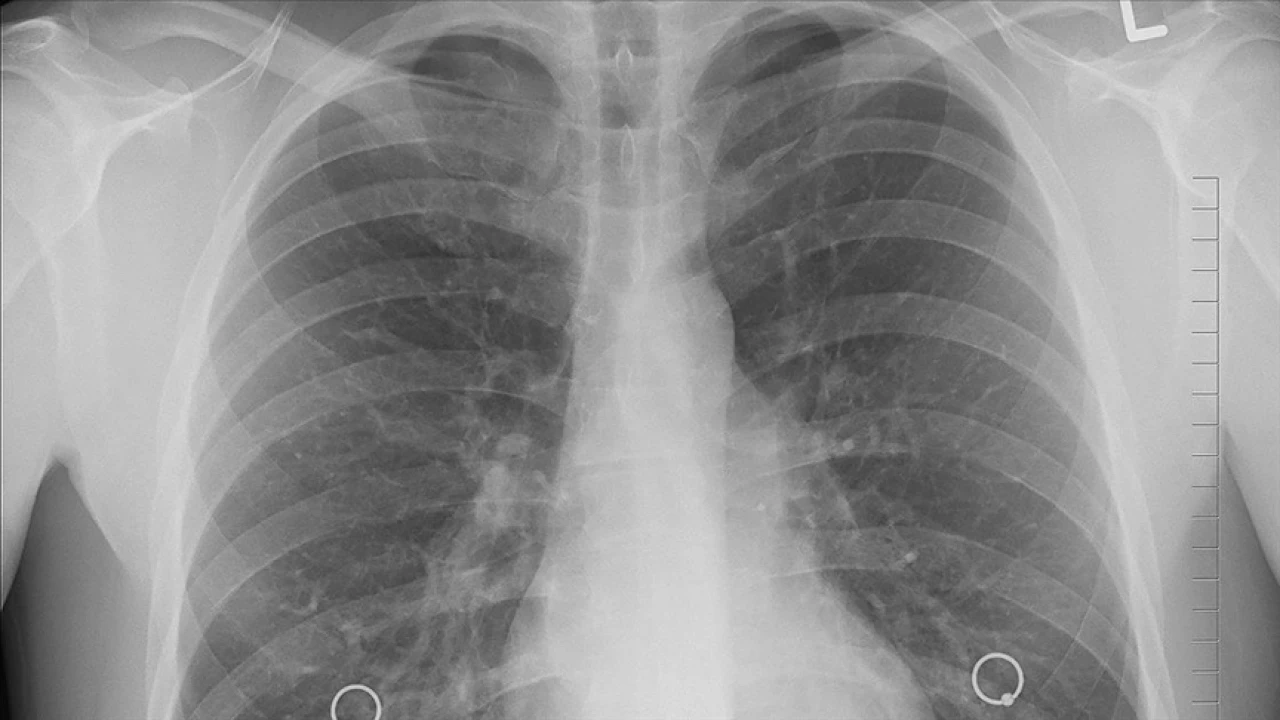

Uzmanlar Uyarıyor: Akciğer Kanserinde Çevresel Faktörlerin Etkisi Hızla Artıyor

Türkiye'de ve dünyada akciğer kanserine bağlı vakalarda sigara içmeyenlerin oranı artarken, uzmanlar çevresel faktörlerin etkisinin her geçen yıl güçlendiğine dikkat çekiyor. Bilimsel çalışmalara göre büyükşehirlerde yaşayan bireylerde akciğer kanseri olasılığı kırsal bölgelere göre yüzde 20 ila 40 daha yüksek. Bu artışın temel nedenleri arasında hava kirliliği, PM2,5 maruziyeti, radon gazı ve ev içi yakıt kullanımı yer alıyor.